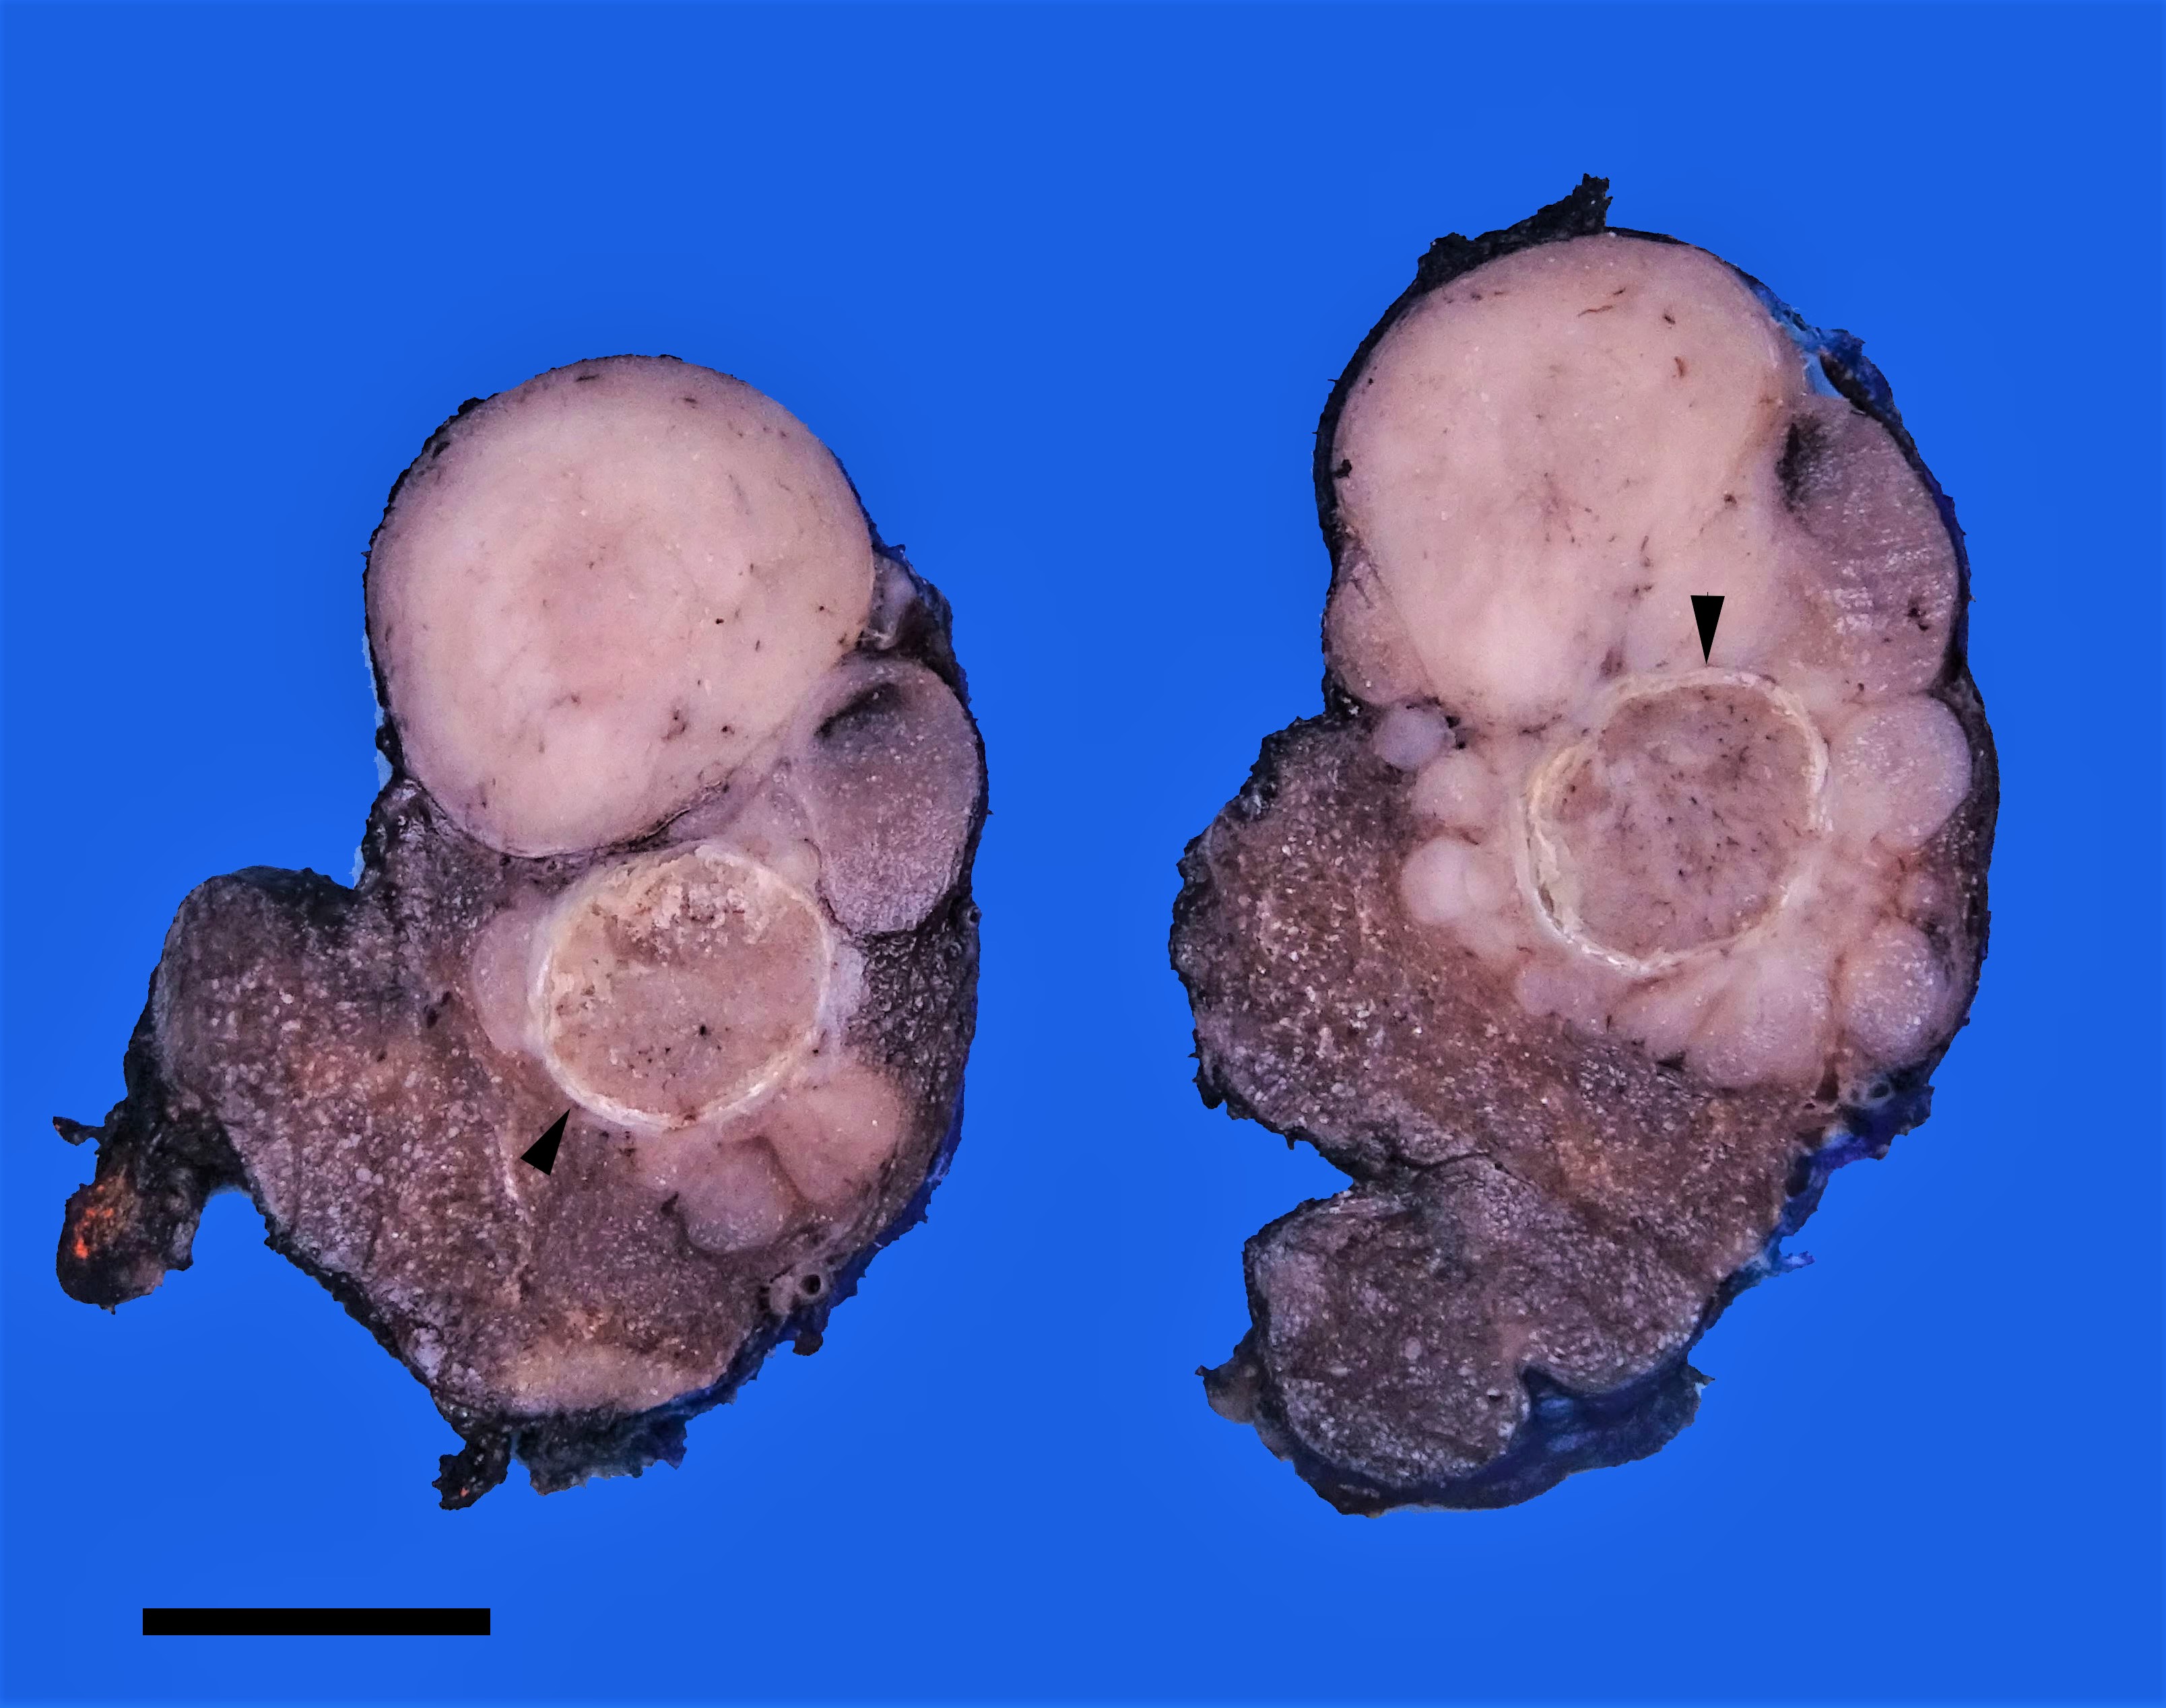

Gross description

- Infiltrative follicular variant has a multinodular to infiltrative tumor border

Gross images